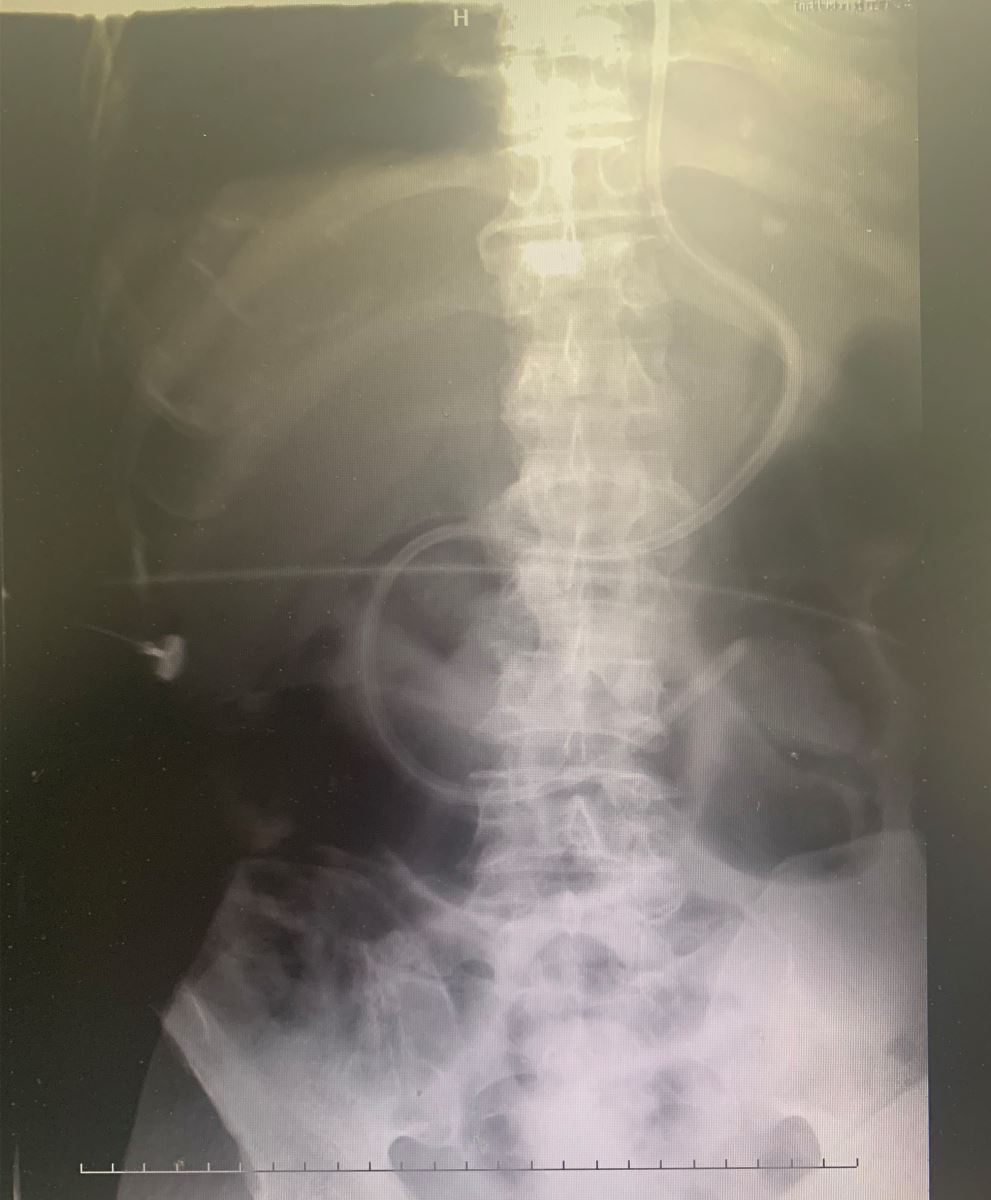

患者赵某,男,主诉神志不清6个月,诊断脑出血,因病情加重转入我院重症医学科,给予脱水利尿、脑保护、抗炎、气管切开机械通气、生命支持等相关治疗。患者在使用普通胃管进行营养供给时已经出现胃功能障碍情况。以往,通常需要借助胃镜将营养管送入空肠内开展营养供给,重症监护科患者病情危重,搬运风险大,即便顺利完成搬运工作,胃镜通过胃幽门的难度也很高,总体而言通过胃镜下管开展手术可谓举步维艰,而徒手盲下营养管更是不现实的。但是,经过重症监护科医护人员的科学研判和周密准备,决定启用一种全新鼻空肠管开展置管,在不借助其它设备的条件下,医生通过精湛的置管技巧徒手盲插,顺利为患者置入十二指肠鼻胃肠管一枚,置管取得圆满成功。目前患者胃部不耐受症状已消失,体征趋于平稳。

据重症医学科副主任曹新林介绍,鼻空肠管的使用对高度肺吸入风险、胃排空障碍、重症胰腺炎、神经系统疾病等症状的患者而言能够有效提供营养支持、改善肠道功能、保护肠粘膜屏障、纠正代谢紊乱、减轻患者胃肠不耐受症状并减少并发症的发生。此次徒手盲下鼻空肠置管术的成功开展对于危重患者意义重大。这不仅使患者痛苦明显减少,同时也极大减轻患者家庭经济负担,是危重患者肠内营养支持的优选方式,也为我院急危重症患者实现空肠营养治疗带来福音。